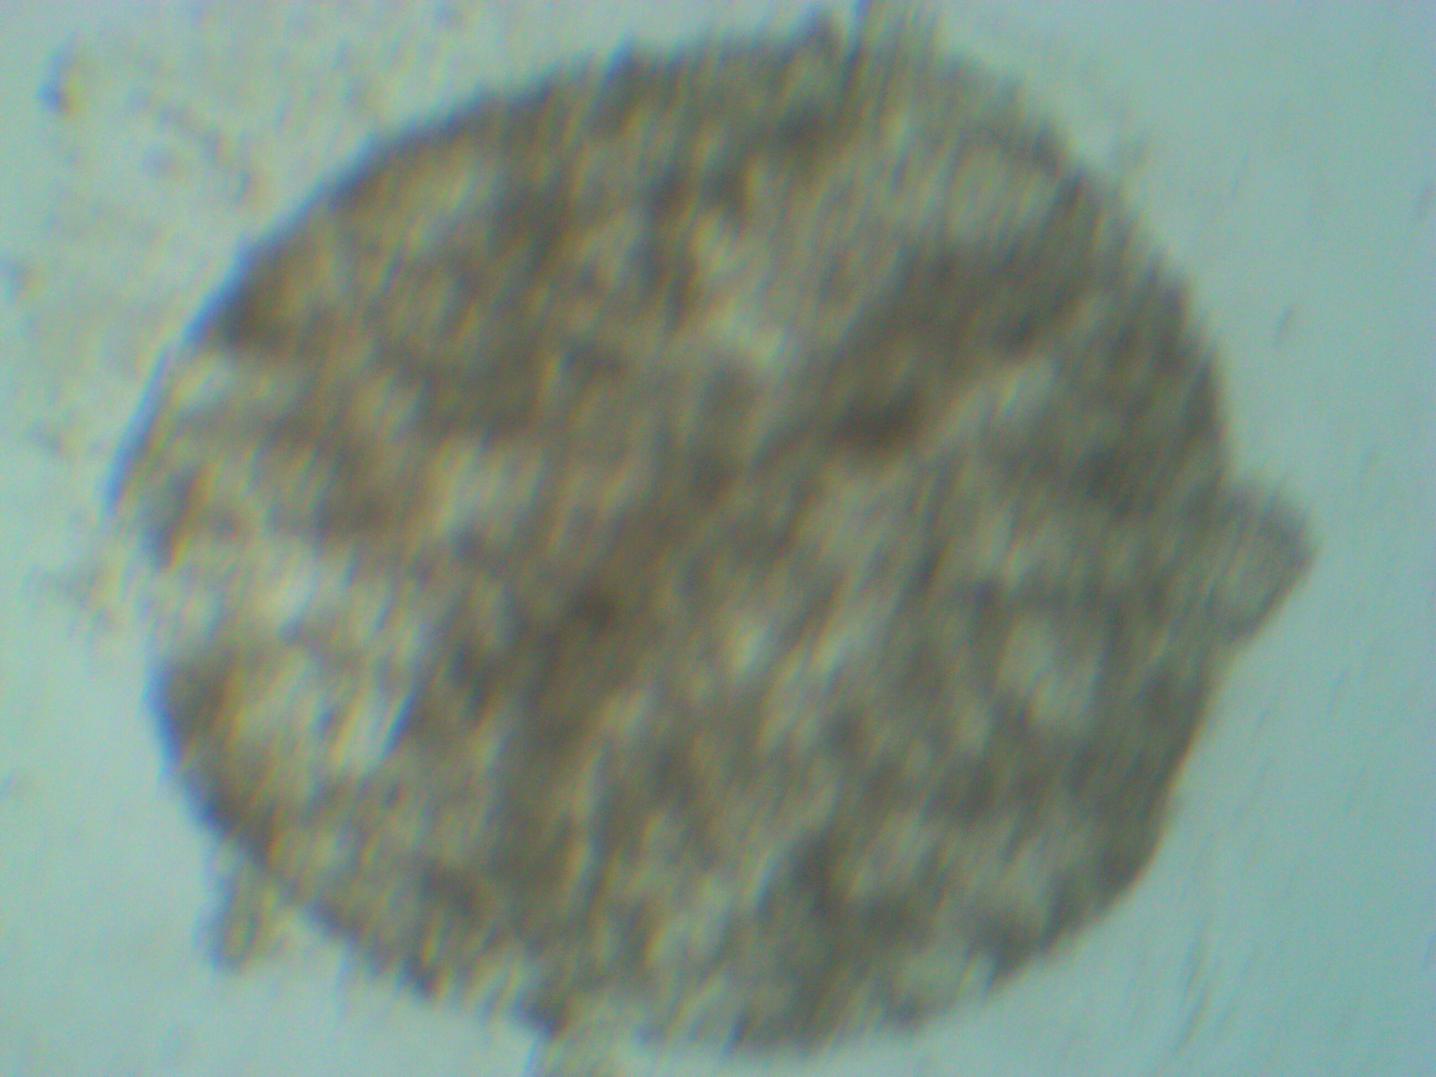

Tomorrow, we will inject 3D spheroids on the first patient and wait to see the outcome and will keep you all updated.

Respected Jahoda says in published study that, we should expect a new hair follicle/s from these injected 3D spheroidal DP cultured cells. Ofcourse i am waiting also report of versican and alkaline phosphate marker report which will conform trichogenic potential of these 3D spheroids.